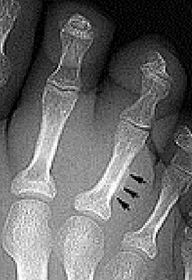

What disease is this? What do the arrows indicate? | Gout Arrows = 'punched out' erosions |